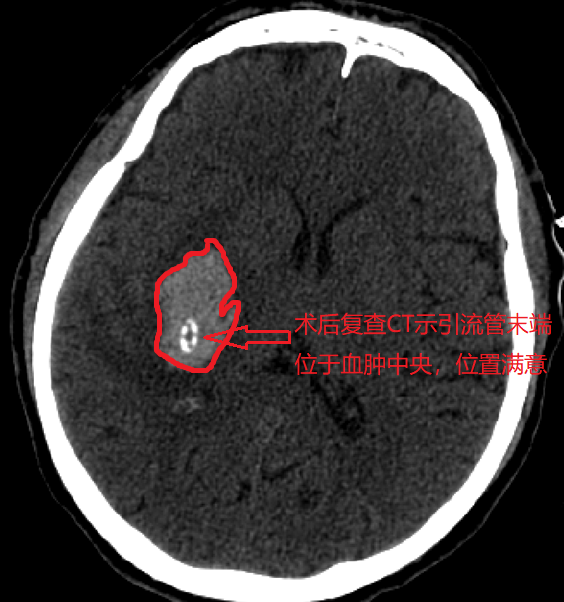

隨后謝竹青主任團(tuán)隊(duì)的肖虎醫(yī)師在3D打印導(dǎo)板導(dǎo)航下實(shí)施血腫精準(zhǔn)穿刺引流術(shù),將一個(gè)直徑5mm的軟管通過導(dǎo)板和穿刺針準(zhǔn)確放置到了血腫中心點(diǎn),成功抽出血腫,耗時(shí)僅30分鐘就完成了手術(shù)。

術(shù)后復(fù)查CT顯示,鐘某引流管頭位置與術(shù)前醫(yī)生在電腦上模擬的位置基本一致,引流管位于血腫的正中央,手術(shù)圓滿成功!術(shù)后第三日,腦內(nèi)血腫引流徹底后,引流管就被拔出。目前,患者已恢復(fù)部分肢體功能。

術(shù)后復(fù)查顱腦CT,證實(shí)穿刺引流管位于血腫的中心,通過腦出血的引流,患者腦組織功能出現(xiàn)了明顯改善和恢復(fù),患者的偏癱明顯減輕,目前正在進(jìn)一步康復(fù)治療中。